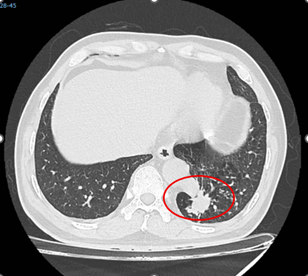

Do đó, người bệnh và bác sĩ thống nhất lựa chọn phương pháp phẫu thuật robot để thực hiện cắt phần phổi bệnh lý. Ngày 12/2/2026, ThS.BSCKII. Nguyễn Văn Việt Thành – Trưởng khoa Ngoại lồng ngực – Bướu cổ, Phó chủ nhiệm Bộ  môn Ngoại khoa Trường Đại học Y khoa Phạm Ngọc Thạch trực tiếp thực hiện. Ca phẫu thuật diễn ra trong khoảng 120 phút và thực hiện suôn sẻ theo đúng kế hoạch: phần phổi biệt lập được cắt trọn mà không tổn thương động mạch chủ ngực xuống, không có biến chứng chảy máu.

Vì không phải banh sườn và các lỗ trocar rất nhỏ, người bệnh ít đau hơn rất nhiều, giảm mất máu và rút ngắn thời gian nằm viện. Minh chứng là ông T. đã hồi phục nhanh chóng và được xuất viện sớm chỉ sau mổ 4 ngày.

Hình: Các bước chính trong phẫu thuật robot cắt phổi biệt lập cho người bệnh T. (Nguồn: Bệnh viện Bình Dân)